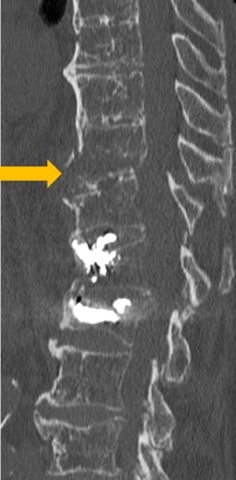

Fractures often manifest themselves through subtle, atypical, and even misleading signs in elderly patients, noted Dr. Catherine Cyteval, a specialist in osteoarticular imaging at Lapeyronie Hospital, CHU Montpellier. She highlighted how osteoporosis, spinal deformities, and osteoarthritis further complicate the interpretation of examinations.

Particular vigilance is required, she continued. Radiologists must monitor the bone cortices in the three planes, carefully examine soft tissue windowing, and use MRI if there is any doubt, she urged. Interventional radiology, particularly cementoplasty, also plays a key role in promoting a rapid return to physical activity and preventing slippage syndrome.

Unstable T11 fracture in a stiff spine in a 92-year-old osteoporotic patient (arrow). The patient had a history of cementoplasty of L1 and L2.